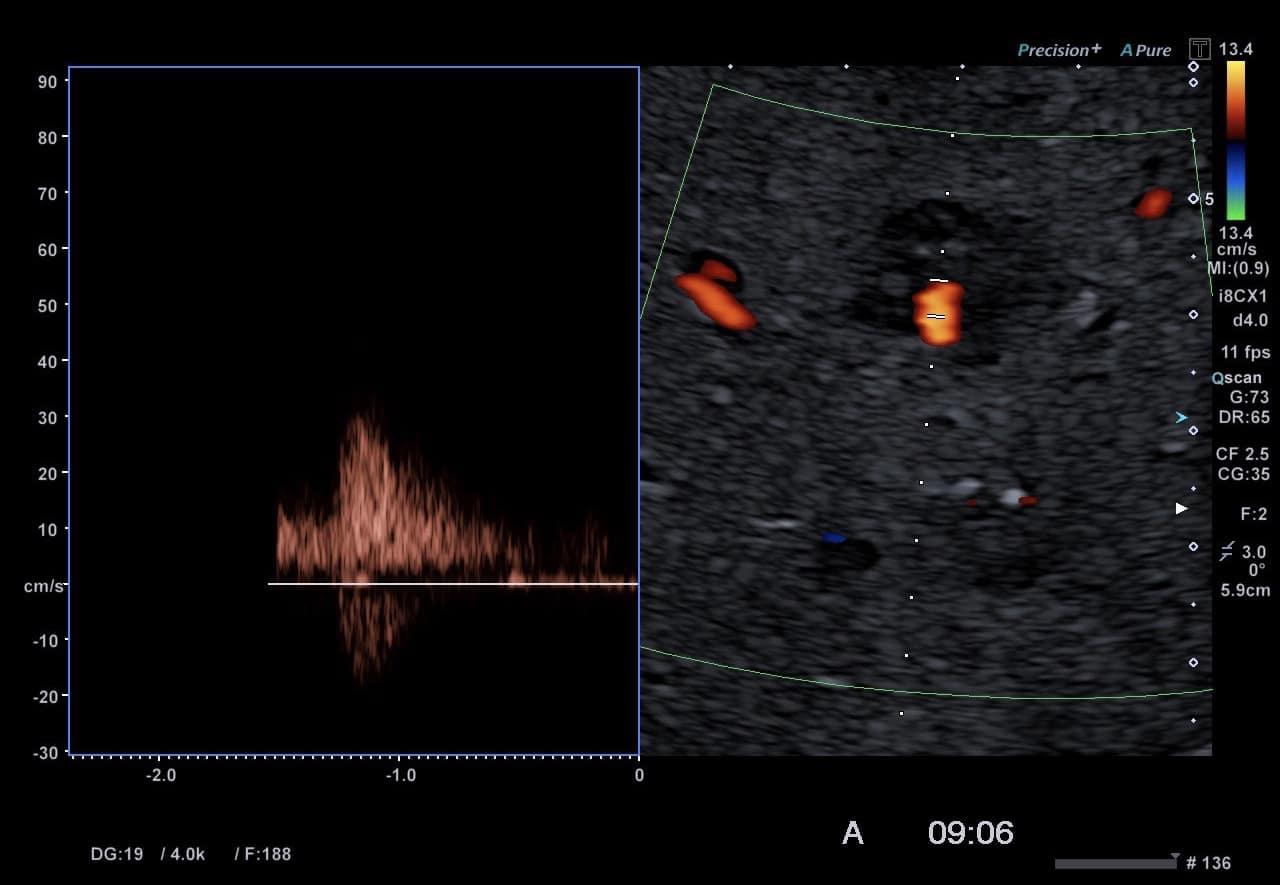

In der Sonografie stellt sich der Befund meist isoechogen zum übrigen Lebergewebe dar. Bei Zugabe eines Ultraschall-Kontrastmittels wird die radspeichenartige Gefäßversorgung dargestellt. Durch das isodense bzw. isointense Verhalten in Computertomographie bzw. Magnetresonanztomographie ist der Befund schwer zu entdecken. Nach Kontrastmittel-Gabe mit wasserlöslichen Kontrastmitteln zeigt sich bei diesen Verfahren ein randständig starkes Kontrastmittel-Enhancement mit zentraler Hypodensität bzw. Hypointensität. Durch die Verwendung gallegängiger Kontrastmittel (Gadoxetic Acid = Primovist (R)) kann in der Magnetresonanztomographie in einer Spätphase mit hoher Empfindlichkeit eine Differenzierung erreicht werden.[1]